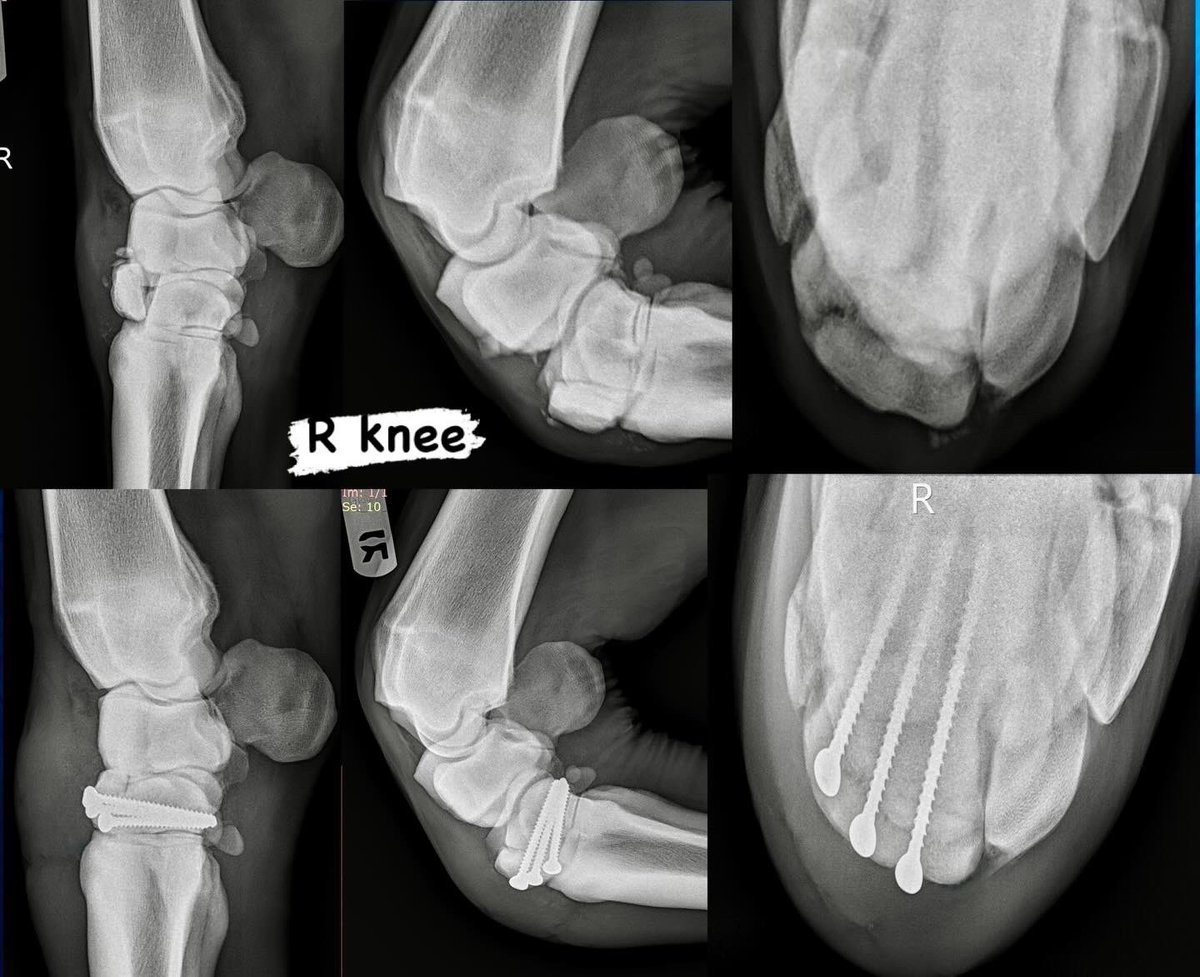

This big beautiful TB filly incurred serious injuries to both of her knees while on the lead in the stretch of a race this weekend- an extremely rare occurrence to experience bilateral slab fractures😱. Fortunately she had immediate expert care from her jockey, the outriders, attending vets, etc and shipped in to us safely. A lot of arthroscopic clean-up and some hardware added to boot and 24-hrs later we have a much happier horse who will go on now and lead a very comfortable life as a broodmare 🔩🔩🔩